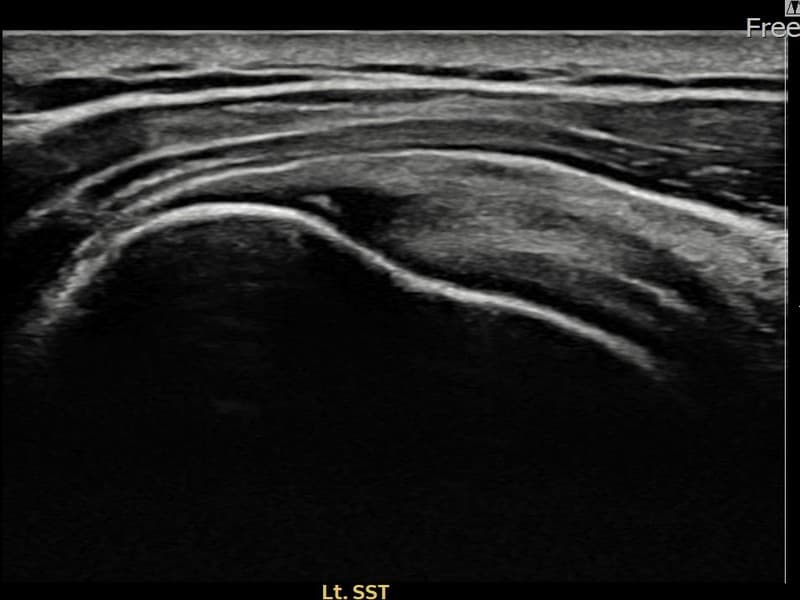

术前

术前超声确认左侧 冈上肌腱 附着部部分撕裂,左侧冈上肌腱回声不连续伴肌腱缺损(9mm × 4mm (肌腱厚度约38%缺损))。术后超声显示撕裂部位充满再生组织,肌腱连续性恢复,回声模式正常化。